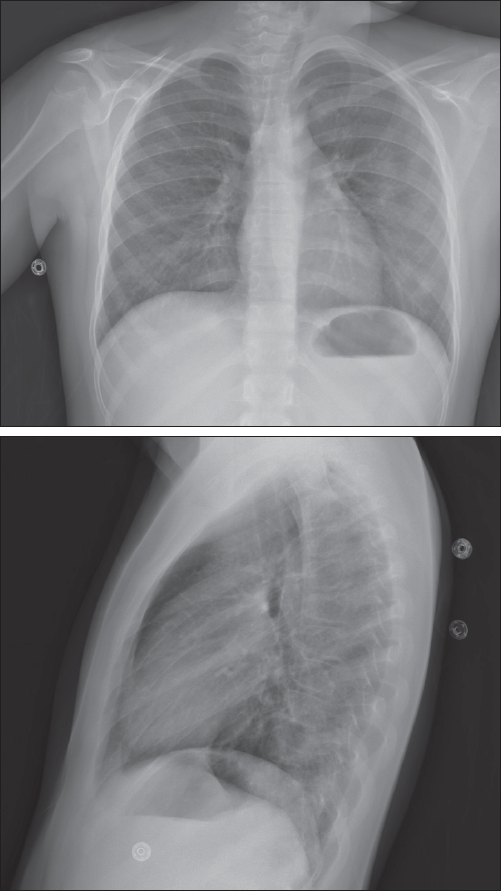

The patient was admitted to the hospital for further workup to include a renal ultrasonogram with biopsy. Sinus radiograph findings were normal. Chest films revealed bilateral increased interstitial markings, with no focal consolidation (Figure 1). A chest CT scan showed diffuse ground-glass opacities in the lungs, consistent with alveolitis, with small focal areas of consolidation (Figure 2). The renal biopsy specimen demonstrated segmental necrotizing and crescentic glomerulonephritis.

Figure 1. Posteroanterior and lateral chest films show bilateral increased interstitial markings, with no focal consolidation.